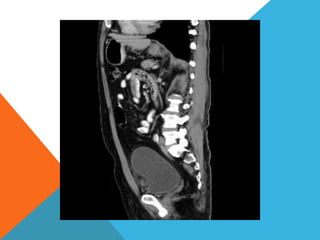

El paciente presentó síntomas de sangrado digestivo y pérdida de peso. Exámenes revelaron gastritis crónica asociada a H. pylori. Un tumor fue descubierto en una colonoscopia normal. La cirugía removió un tumor fibroide solitario, una rara neoplasia mesenquimal que usualmente crece lento y tiene bajo potencial de malignidad. El pronóstico después de la remoción quirúrgica es generalmente bueno.